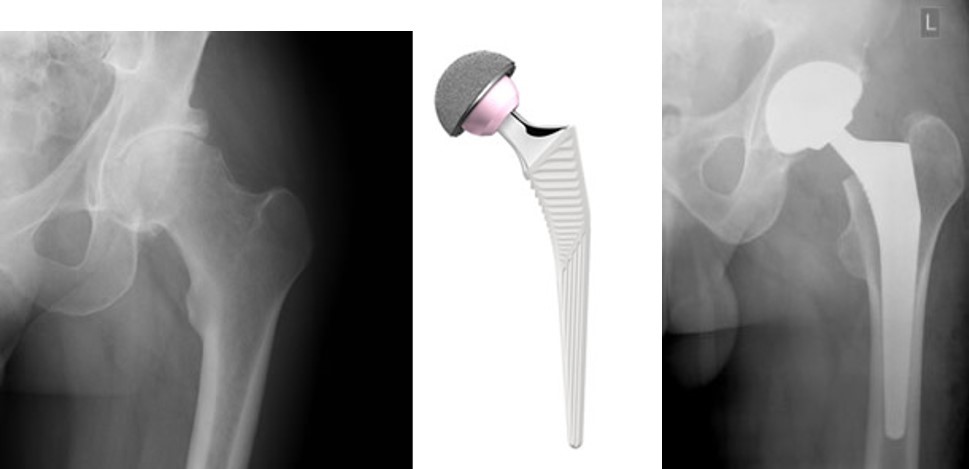

X-rays showing before and after hip replacement surgery, with the type of prosthetic (artificial) hip joint used in the middle.

Image: © Thackray Medical Museum